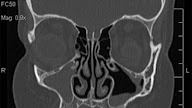

Common causes of chronic sinusitis include: 1. nasal polyps. these tissue growths can block the nasal passages or sinuses. dua. deviated nasal septum. a crooked septum — the wall between the nostrils — may restrict or block sinus passages, making the symptoms of sinusitis worse. 3. other medical conditions. the complications of conditions such as cystic fibrosis, hiv and other immune system-related diseases can lead to nasal blockage. 4. respiratory tract infections. infections in your respirat Take these a 4 year times sinusitis steps to reduce your risk of getting chronic sinusitis: 1. avoid upper respiratory infections. minimize contact with people who have colds. wash your hands frequently with soap and water, especially before meals. 2. manage your allergies. work with your doctor to keep symptoms under control. avoid exposure to things you're allergic to whenever possible. 3. avoid cigarette smoke and polluted air. tobacco smoke and air contaminants can irritate and inflame your lungs and nasal passag

Sinus infections may cause chronic sinus inflammation and symptoms. if you have more than three sinus infections in a year or have symptoms longer than 12 weeks, you could have chronic sinusitis. more than 50 percent of people with moderate to severe asthma also have chronic sinusitis. “typically acute sinusitis resolves by 10 days, but if not, then the possibility of a bacterial infection should be considered,” says dr. chen. “getting one or 2 sinus infections a year is. You're at increased risk of getting chronic sinusitis if you have: 1. a deviated septum dua. nasal polyps tiga. asthma 4. aspirin sensitivity lima. a dental infection 6. an immune system disorder such as hiv/aids or cystic fibrosis 7. hay fever or another allergic condition 8. regular exposure to pollutants such as cigarette smoke. Recurrent. this means the infection comes back again and again. it means 3 or more episodes of acute sinusitis in a year. the sinuses are air-filled spaces (cavities) near the nose.